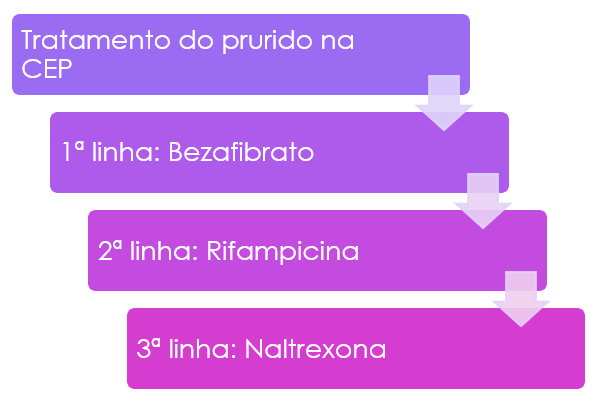

O ácido ursodeoxicólico – UDCA (ursacol ®) é um variante de sais biliares que tem a característica de ser mais hidrofílico (mais solúvel em água) que a maioria dos sais biliares normalmente presentes na bile. Quando administrado em doses terapêuticas (13 a 15 mg/kg/dia), passa a constituir cerca de 40% do pool de ácidos biliares na bile, que torna-se menos detergente e tóxica. Além disso, parece ter efeito mudando aspectos de imunidade nos hepatócitos e canais biliares, estimulando a secreção hepatobiliar (reduzindo a colestase) e tem uma ação anti-apoptótica de mecanismo ainda não adequadamente esclarecido. Seu uso tem sido intensamente investigado na CEP. Há evidências significativas, porém não em todos os estudos, de melhora nos sintomas, achados histológicos (biópsia), exames laboratorias e na colangiografia. A dose utilizada na maioria dos estudos é de 13-23 mg/kg/dia dividida em 3 ou 4 vezes ao dia. Outros medicamentos, como imunossupressores, colchicina e a d-penicilamina não se mostraram eficazes. A associação do imunossupressor micofenolato mofetil (cellcept ®) com o UDCA também não mostrou vantagens.

Outros medicamentos mais modernos estão em pesquisa, ainda sem dados suficientes para o seu uso. Destacam-se inibidores IBAT, agonista FXR (ácido obeticólico – recentemente retirado do mercado), agonistas PPAR não fibratos (elafibranor e seladelpar), probióticos e ácido norucólico.